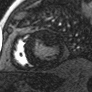

心脏成像 --- 压缩感知电影

自由呼吸,无需屏气

捕获全心动周期数据

临床价值

成像速度和图像质量同时提升

定量数据更精准

心脏MR适用人群更广

实例展示

压缩感知

传统实时

传统分段

心脏电影---房颤病人图像质量对比

感染性心肌疾病—心肌炎合并心肌缺血